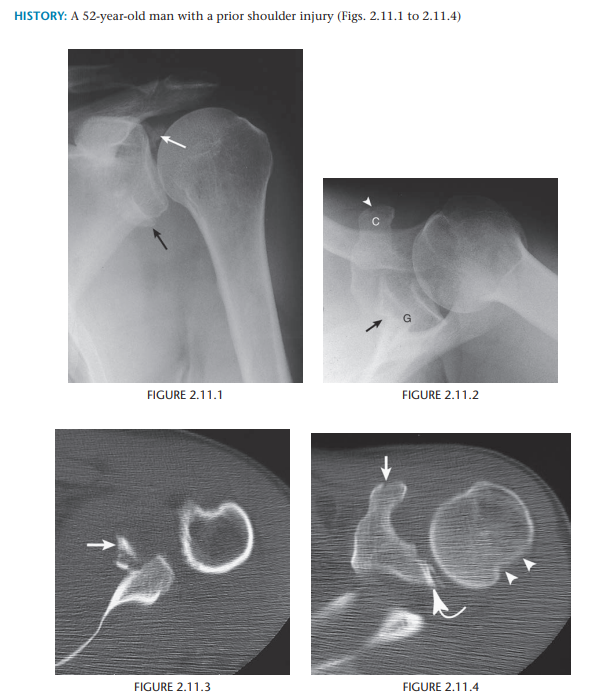

Bony Bankart lesion of the shoulder with

an associated Hill–Sachs deformity of the humeral head caused by anterior glenohumeral dislocation

Traumatic anterior dislocation of the shoulder

Posterolateral humeral head compression fracture (Hill-Sachs deformity)